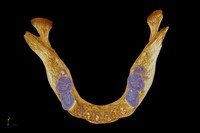

Medieval human mandible (lower jaw bone).

MacKenzie, Kevin.Date: 2011